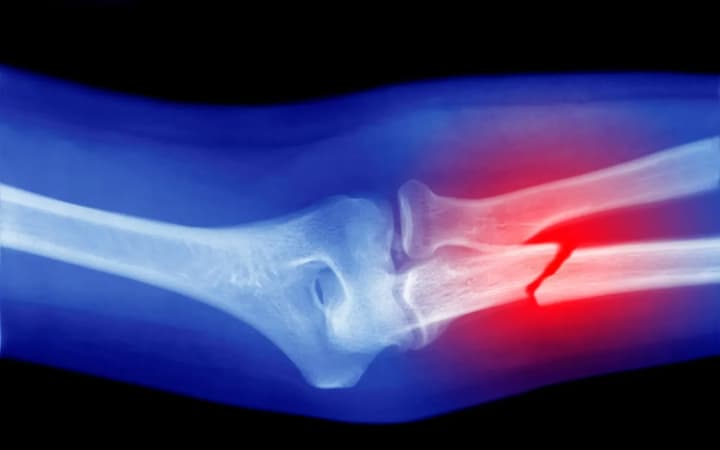

Огляд 60 наукових робіт показав, що мікропластик впливає на клітини кісткової тканини, стимулюючи утворення остеокластів. Це порушує баланс відновлення кісток, що підвищує ризик остеопорозу та переломів.

Протягом життя кістки постійно оновлюються, але при остеопорозі руйнування відбувається швидше, ніж регенерація. Новий аналіз, опублікований у журналі Osteoporosis International, додає мікропластик до списку факторів ризику цієї хвороби поряд із віком, генетикою, дієтою чи шкідливими звичками.

Ці фактори призводять до руйнівних процесів, що ослаблюють кісткову структуру та підвищують ризик переломів.